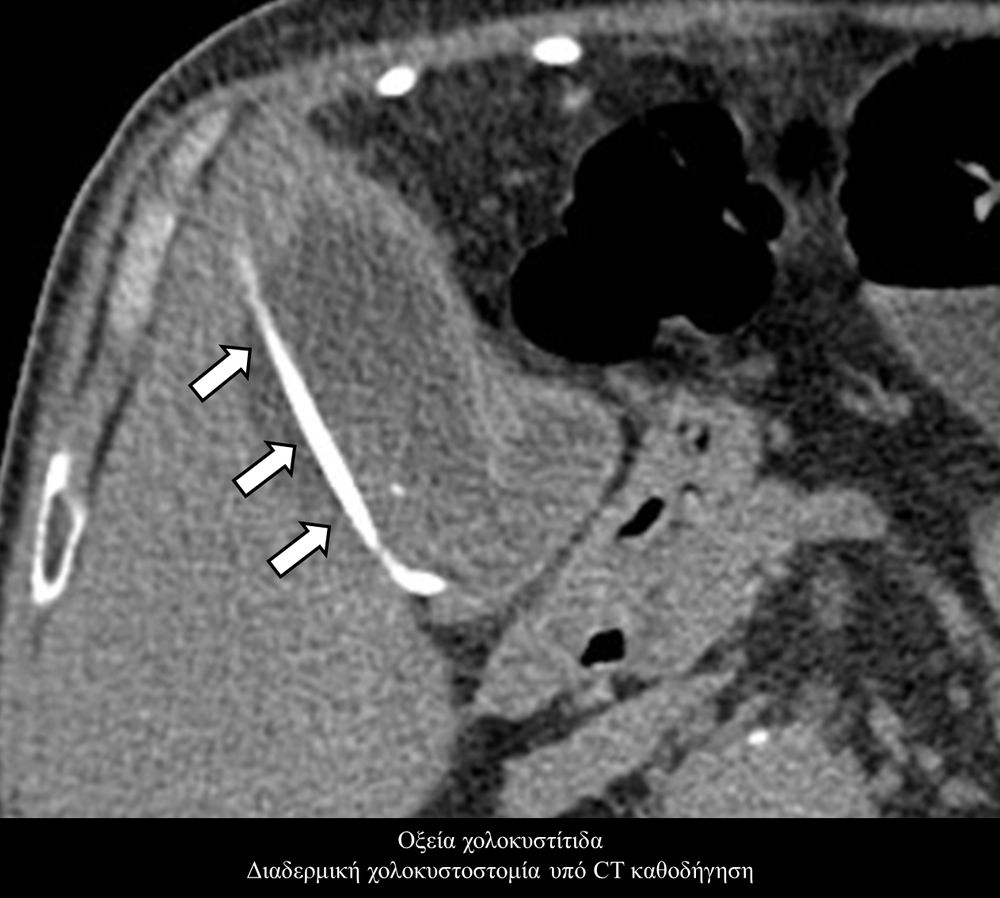

Η προσπέλαση σε όλες τις περιπτώσεις γίνεται διαδερμικά και η νοσηλεία του ασθενούς διαρκεί συνήθως μία ημέρα και ο ασθενής επιστρέφει στο σπίτι του την επομένη.